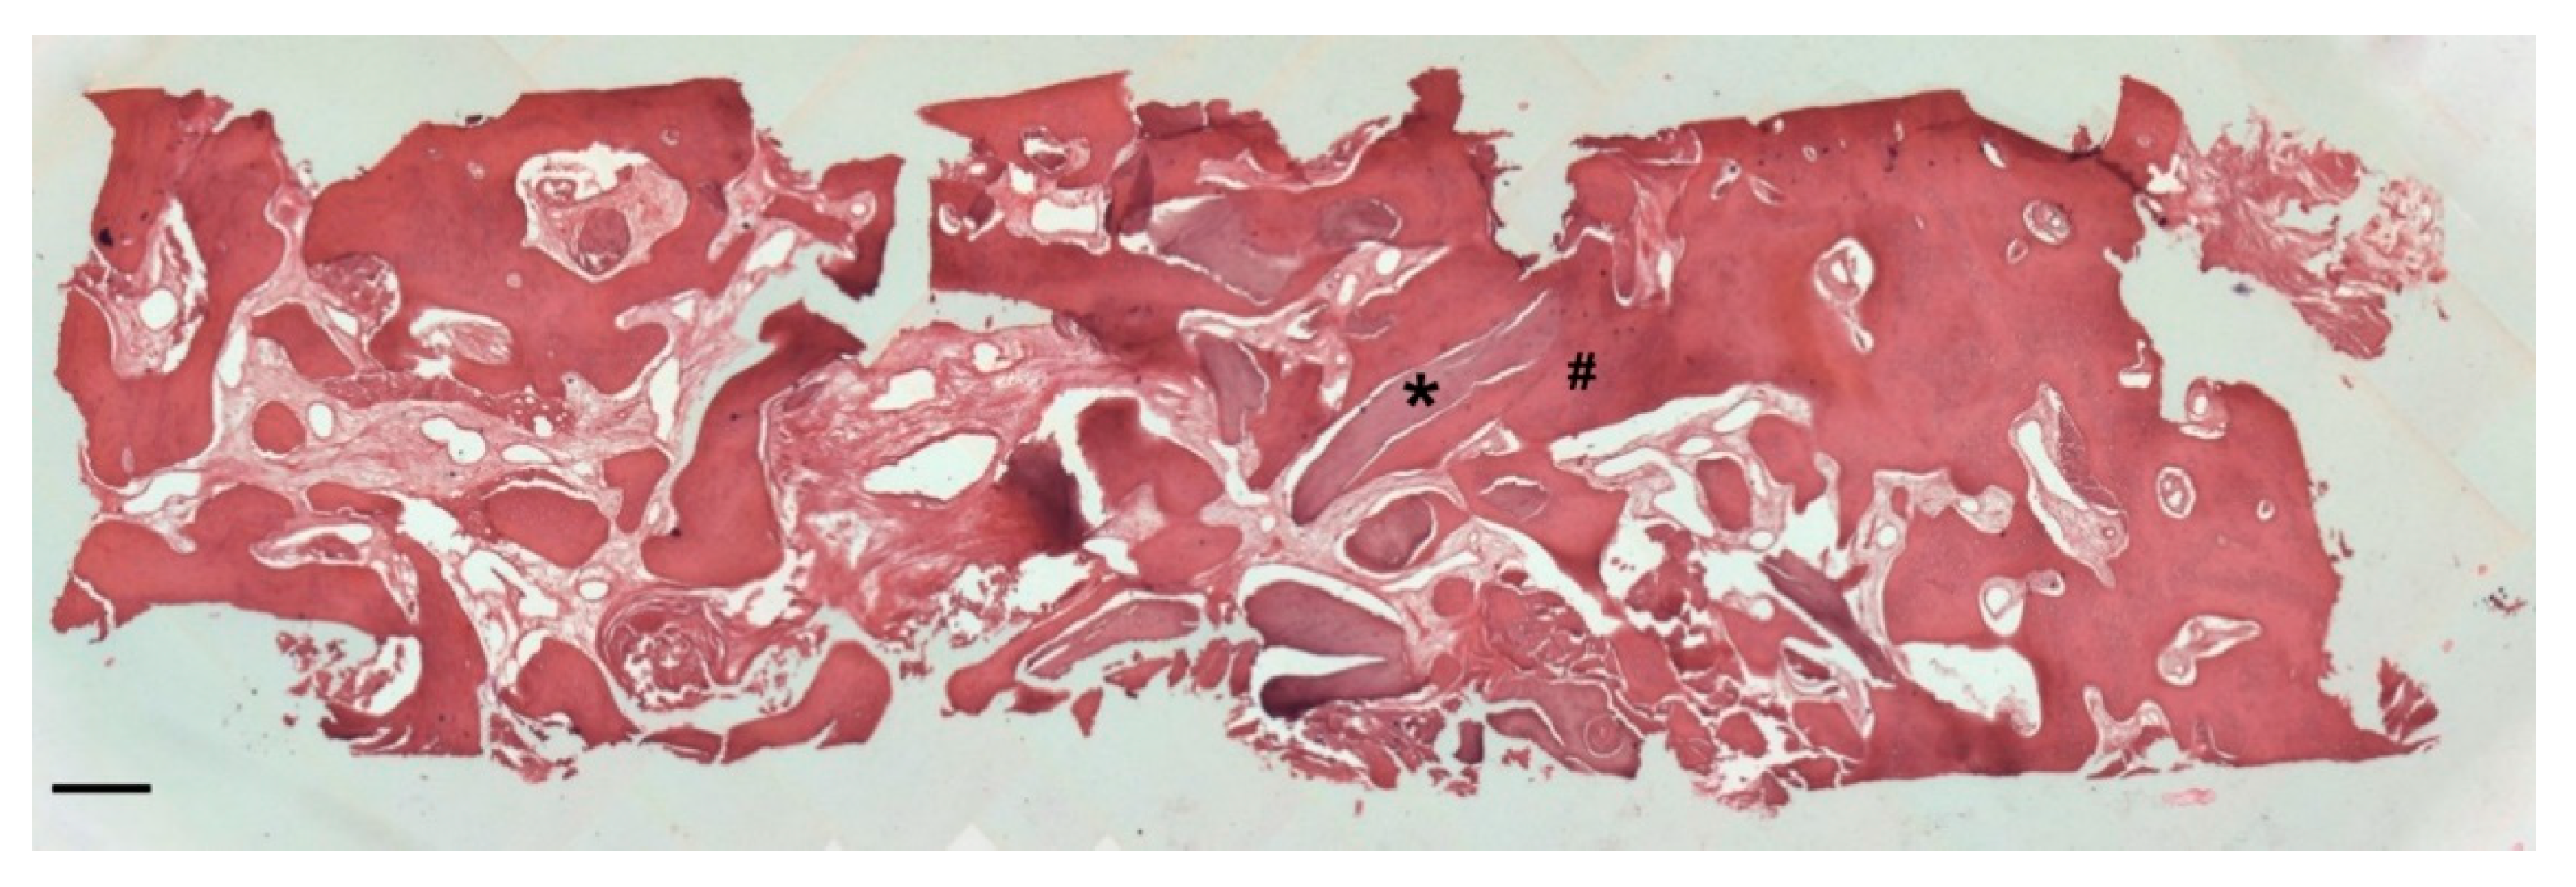

Histology